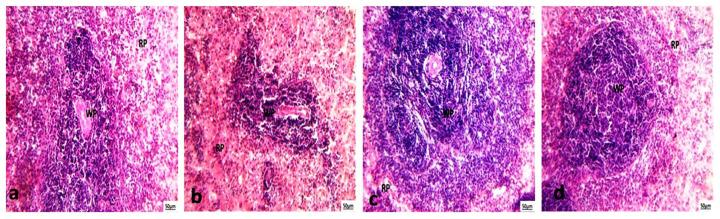

Cisplatin is a widely utilized chemotherapy drug effective against various cancers, yet its use is often constrained by severe toxicity to healthy organs, including the liver, kidneys, and spleen. This study explored the protective role of , a microalga known for its antioxidant and anti-inflammatory properties, against cisplatin-induced organ damage. The research focused on modulating oxidative stress, inflammation, and the Nrf2 signaling pathway. The experimental design included four groups: a control group receiving saline, a cisplatin group administered 1.34 mg/kg weekly for three months, a group receiving 150 mg/kg daily, and a combined cisplatin/ group. Cisplatin treatment significantly elevated oxidative stress markers, such as lipid peroxidation and nitric oxide, while increasing pro-inflammatory cytokines (TNF-α, IL-12, IL-6) and reducing antioxidant capacity. Additionally, liver and kidney function markers were markedly impaired, and histopathological analysis revealed structural damage in the liver, kidneys, and spleen. Conversely, supplementation mitigated these effects, restoring oxidative stress markers, cytokine levels, and organ function to near-normal values. Microscopic examination confirmed that effectively prevented cisplatin-induced structural damage. Notably, while cisplatin increased Nrf2 expression as an adaptive response to oxidative stress, attenuated this effect, reflecting its potent antioxidant capabilities.

顺铂是一种广泛应用的化疗药物,对多种癌症有效,但其使用常因对包括肝脏、肾脏和脾脏在内的健康器官具有严重毒性而受到限制。本研究探讨了以其抗氧化和抗炎特性而闻名的微藻对顺铂诱导的器官损伤的保护作用。该研究聚焦于调节氧化应激、炎症和Nrf2信号通路。实验设计包括四组:接受生理盐水的对照组、每周给予1.34 mg/kg共三个月的顺铂组、每天接受150 mg/kg的微藻组以及顺铂/微藻联合组。顺铂治疗显著提高了氧化应激标志物,如脂质过氧化和一氧化氮,同时增加了促炎细胞因子(TNF-α、IL-12、IL-6)并降低了抗氧化能力。此外,肝脏和肾脏功能标志物明显受损,组织病理学分析显示肝脏、肾脏和脾脏存在结构损伤。相反,微藻补充减轻了这些影响,使氧化应激标志物、细胞因子水平和器官功能恢复到接近正常的值。显微镜检查证实微藻有效地预防了顺铂诱导的结构损伤。值得注意的是,虽然顺铂增加了Nrf2表达作为对氧化应激的适应性反应,但微藻减弱了这种作用,反映了其强大的抗氧化能力。